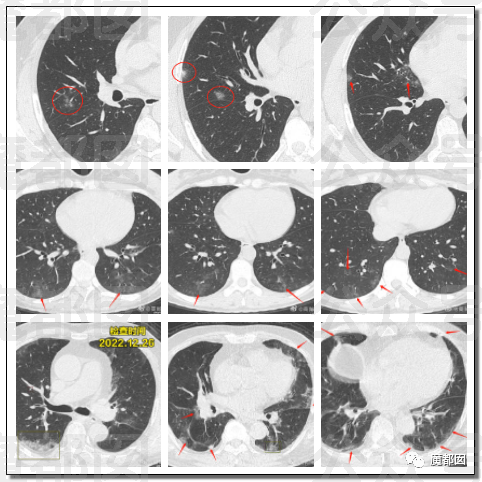

这个我们在过去几天的文章中写过多次,我们好像是所有公众号里最早写这波肺炎的,今天再给大家一个案例,这批肺炎总量还真的不小: